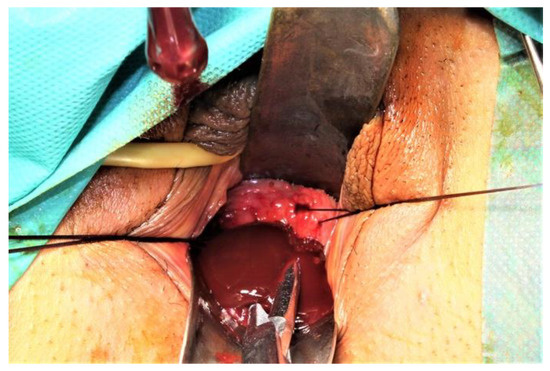

We present a case of HWWS diagnosed in our department in a 16-years-old girl who presented for severe left-lower quadrant pain, nausea, and urinary symptoms. Her menarche started the year before presentation, and monthly bleeding was regular; lasting 4 days; and was accompanied by increasing abdominal pain, nausea, urinary symptoms, and sometimes vomiting. She was not sexually active. During her first gynecology referral from another institution, she was recommended contraceptive pills for severe dysmenorrhea, which she refused. In the first visit in our hospital, the physical examination of the abdomen revealed mild abdominal tenderness of the left lower abdominal quadrant. Abdominal ultrasound (US) was performed but was considered not sufficiently informative; we only observed a voluminous cystic mass corresponding to hematocolpos. Therefore, after a careful explanation of the procedure and counseling, the girl and her parents decided to accept trans-rectal US examination. This revealed a didelphys uterus with a mild hematometra of the left hemiuterus, normal right hemiuterus and an impressive left-side collection, inferior and in connection with the left hemiuterus, corresponding to a hematocolpos. Both ovaries were present and of normal aspect and size (Figure 1). To better describe the findings and in view of the frequent association of congenital anomalies of the reproductive system with renal anomalies, an MRI was recommended and performed. The pelvic MRI showed two clearly separated hemiuteri (didelphys uterus), with mild left hematometra and normal right hemiuterus, mild left hematosalpinx, and an impressive left hemivagina, connected to the left hemiuterus, distended by a content whose signal was similar to methemoglobin, suggesting an obstructed hematocolpos (Figure 2A,B). Blood analysis was within normal range, except CA 125, which measured 89, 62 u/mL (more than the normal range for that age).

Figure 2. MRI of the pelvis. (A). Hematocolpos and left hemiuterus. (B). Hematocolpos and left hemiuterus. The pelvic MRI showed two clearly separated hemiuteri (didelphys uterus), with mild left hematometra and normal right hemiuterus, mild left hematosalpinx and an impressive left hemivagina, connected to the left hemiuterus, distended by a content whose signal was similar to methemoglobin, suggesting an obstructed hematocolpos.